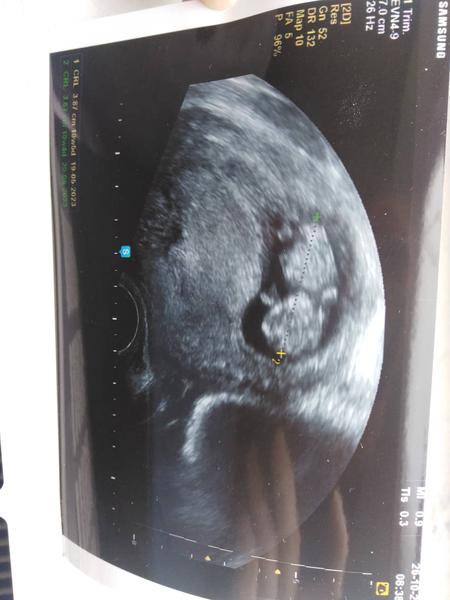

Ahojky tak přikládám fotečku z druheho utz 😀 miminku se daří dobře už je to macek má 3,8 cm a odpovídá 10plus 5 🙂 Je to pěkně divoké mimnko pan dr měl co dělat aby ho zaměřil 😀 jinak zánět dr furt vidí jen mi řekl, že musim vydržet, že dřív jak po 12 týdnu mi pry nemůže nic dát ☹ hold do 14 tydne než se přeléčím se prý musím smířit s tím, že jsem v pelíšku nepoužitelná ☹ na což teda nejsem vůbec zvyklá 😀 10. 11. jdeme na velký utz a doufáme, že budeme mít štěstí na dobrého doktora a na to, že miminko bude správně natočene a dozvíme se jestli to bude ta holčička byla některá z vás už v Olomouci? Vůbec nevim co tam je za dr. stejně tak v porodnici ve fakultce trochu se bojim abychom byli spokojení potom až dojde na porod 🙂 přeci jen velká nemocnice. a recenze jsou všelijaké 😀 je tu někdo kdo se nechá překvapit a kdo si nenecha říct pohlaví miminka ?

@nikolaa64 prvorodičky uciti kopance nejdřív kolem 20 týdne a mi co už měli mimi můžem cítit už od 16 týdne dřív je to velmi nepravděpodobné, ale kdo ví třeba se vymikáš pravidlům 🙂 já cítím jen bodavou bolest to bude asi zvěčující se děloha zítra mne čeká druhý utz. tak pošlu zas fotečku 🙂